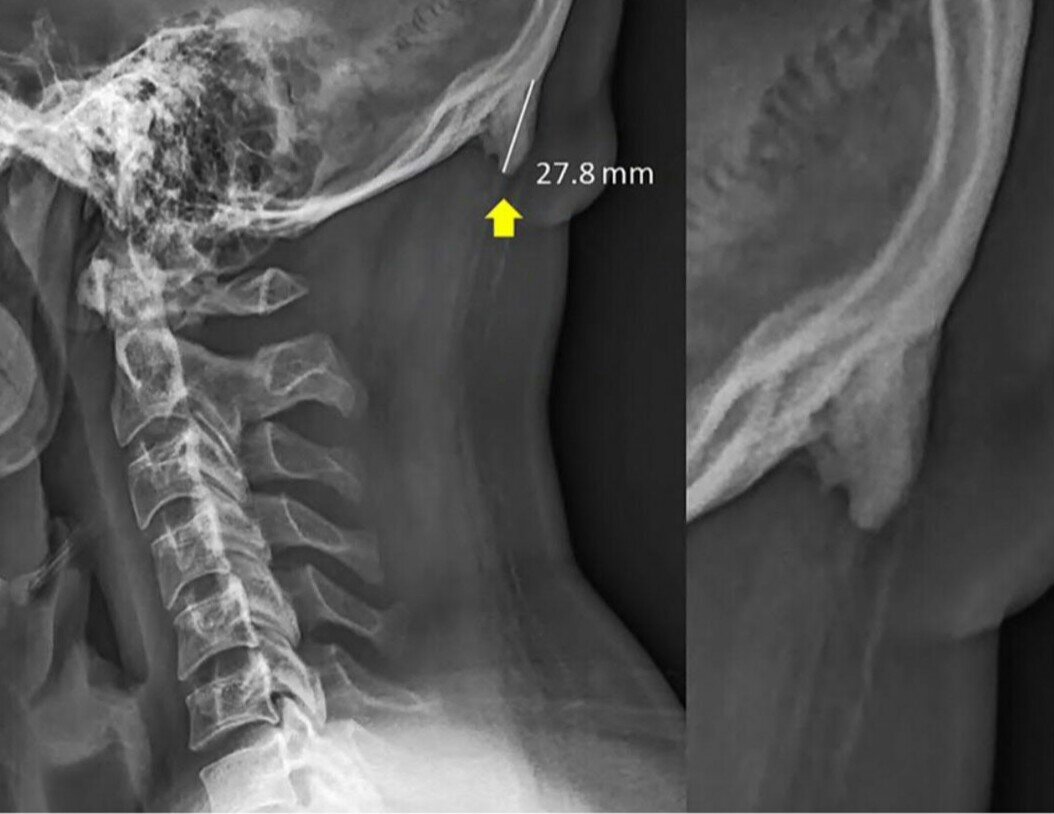

• Процесс эволюции у людей остановился. Сейчас новые задачи появляются раньше, чем мы успеваем приспособиться. Но все же жизнь заставляет нас трансформироваться под современные нужды, и от постоянного использования телефона у нас, например, появляется кость в голове.

Точнее не кость, а наружный затылочный выступ. Он сзади, на затылке, прямо над шеей. Раньше этот выступ считался очень редкой находкой, теперь же он часто встречается у молодёжи и у людей до 30-ти.

Считают, что он появляется, чтобы распределить и уменьшить нагрузку между мышцами. Мы ещё до появления смартфонов создавали нагрузку на шею, но не в таком объёме как сейчас.